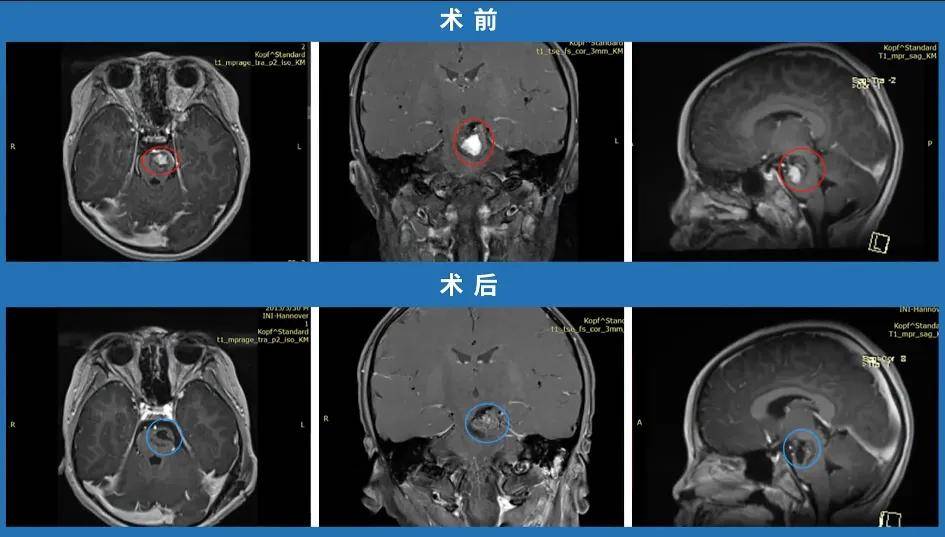

黄女士的脑干海绵状血管瘤术前影像资料

直至2016年10月初,黄女士开始出现头晕与手指发麻的临床症状。她立即就医,神经外科主任审阅其病史与影像资料后表示:“病灶所处位置极为凶险,位于脑干延髓右侧腹侧面,手术风险极高,可能导致瘫痪、植物人状态甚至死亡,因此建议采取保守治疗。或许现阶段进行手术,效果还不如维持当前状态”。别无选择,黄女士及其家人只能接受保守治疗方案,这虽是当时唯一可行的选择,却也为此后的病情危机埋下隐患。

手术日期如期而至,巴特朗菲教授为黄女士实施了延髓海绵状血管瘤切除手术。术后第一天清晨,黄女士恢复了完全自主呼吸。睁开双眼的那一刻,她第一眼便看到了巴教授,脱口而出:“巴教授,您好!”下意识地,她竖起大拇指为教授点赞——手部能够活动,脚部能够活动,意识清晰,尝试吞咽一口口水,吞咽功能正常,眼睛也能正常闭合,面瘫症状已然消失。

那一刻,全身涌动的愉悦难以言表,所有煎熬与等待都获得了最好的回报。术后第二天下午,黄女士便从ICU转入普通脑外科病房,术后两周,她顺利出院,开启了康复历程。